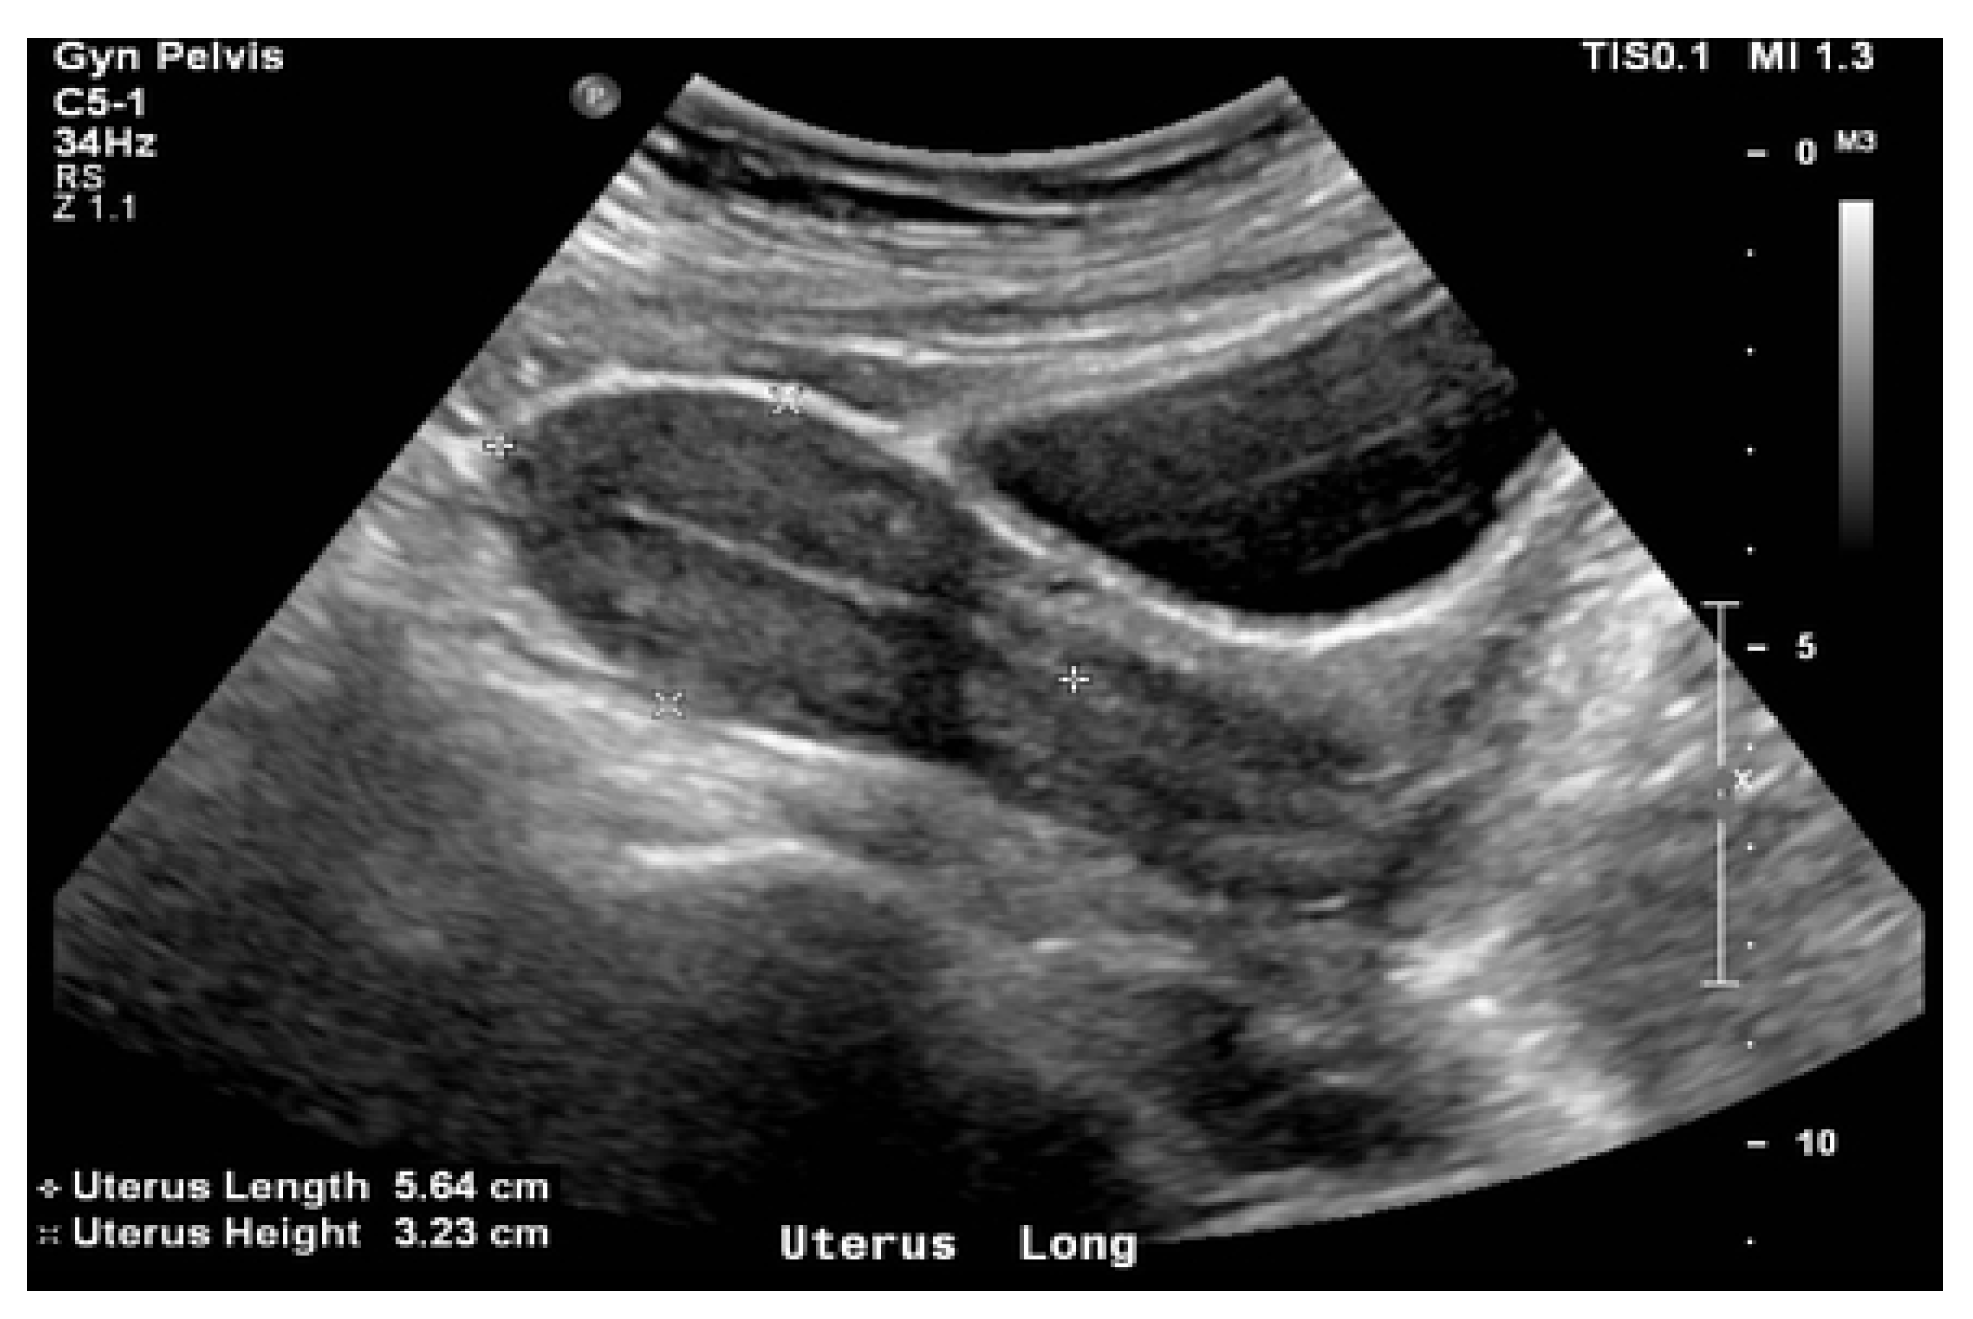

Figure 3.

General aspect of the uterus and of the cervix during an intravaginal ultrasound.